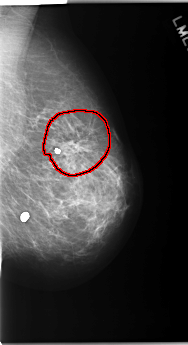

FILE: C_0171_1.RIGHT_CC.OVERLAY

TOTAL_ABNORMALITIES 1

ABNORMALITY 1

LESION_TYPE CALCIFICATION TYPE PLEOMORPHIC DISTRIBUTION CLUSTERED

ASSESSMENT 4

SUBTLETY 4

PATHOLOGY MALIGNANT

TOTAL_OUTLINES 1

BOUNDARY